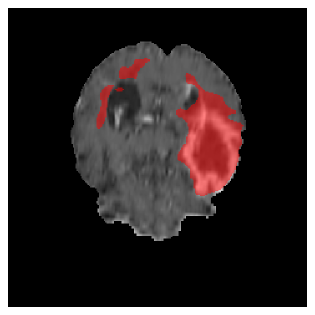

Appendix A Qualitative results

Figures 4 and 5 present the segmentation results for a patient from the BRATS dataset, visualized on a randomly selected slice. Figure 4 illustrates how tumor segmentation evolves over multiple episodes in S1 across different approaches including cumulative, naive, our approach, and the best buffer-free strategy (SI, =2). The cumulative approach, which trains on all encountered datasets together, maintains segmentation consistency across episodes but introduces significant amounts of false positives, particularly in the upper left area of the brain images. These misclassifications highlight its inability to generalize well across datasets despite access to all previous data. The naive approach, which learns sequentially without any continual learning strategy, suffers from severe catastrophic forgetting. While it initially segments well, performance deteriorates over episodes, leading to a near-complete loss of segmentation capability by the final episode. The SI (=2) approach, a regularization-based buffer-free CL strategy, performs reasonably well in early episodes but shows a significant performance decline over time. By the last episode, much of the tumor was no longer segmented, indicating difficulty in retaining prior knowledge. In contrast, our proposed approach initially produces more false positives but progressively refines its segmentation. By the final episode, it accurately retains the tumor region while minimizing misclassifications, demonstrating strong knowledge retention and adaptability across episodes. This suggests that our approach effectively mitigates catastrophic forgetting while maintaining segmentation performance over sequential learning.